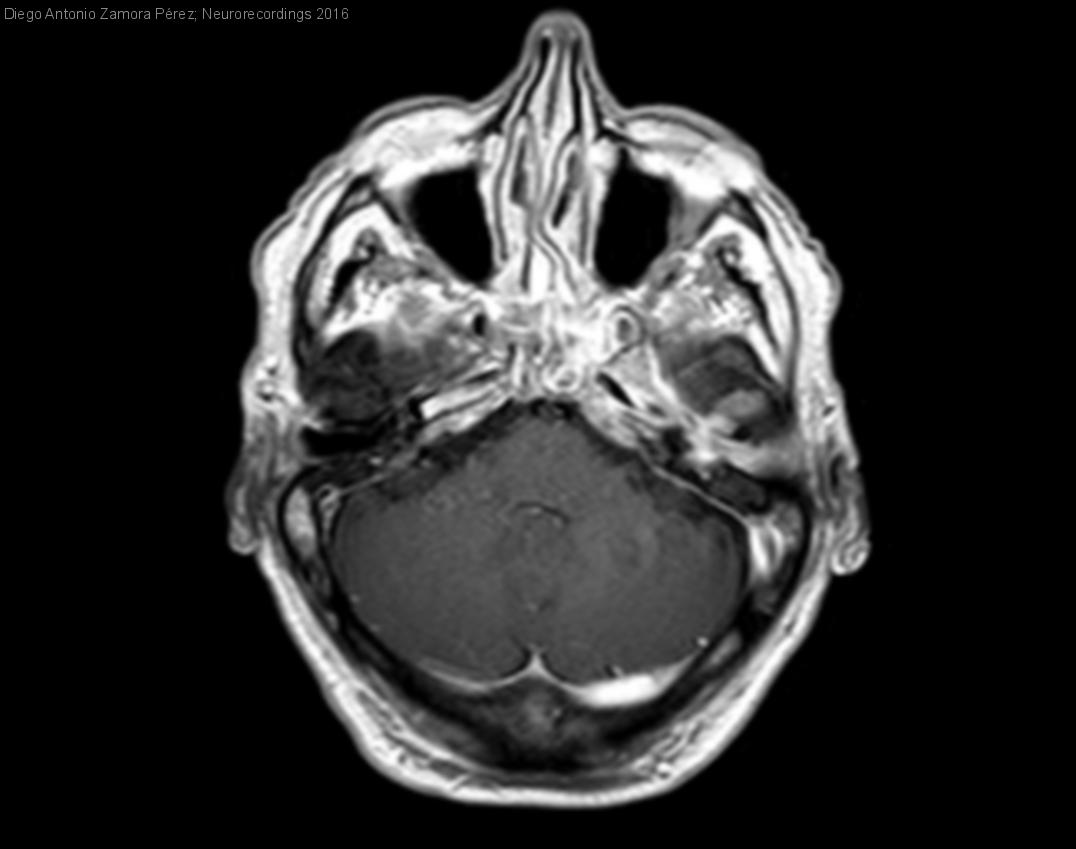

Varón de 69 años con cuadro progresivo de cefalea, diplopia binocular y parálisis de nervios craneales bajos

Diagnóstico final: Osteomielitis de base de cráneo por Pseudomona aeruginosa

Varón de 69 años con antecedente personal de HTA y DM tipo 2. El paciente es ingresado por un cuadro de instauración progresiva y de varias semanas de evolución consistente inicialmente en cefalea de características...